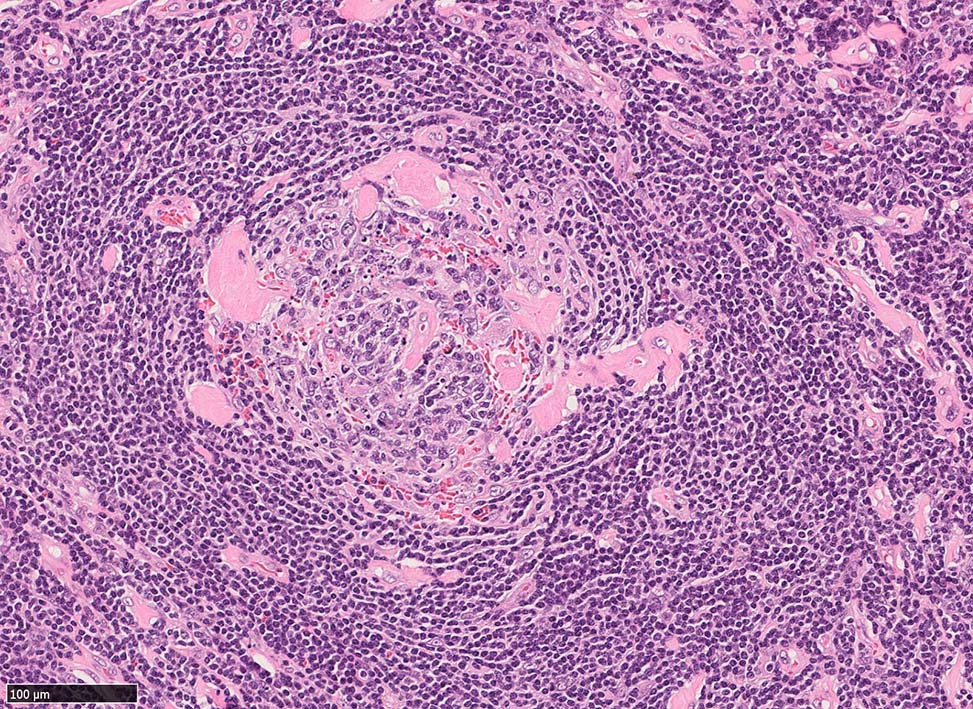

硝子血管型 hyaline vascular type: 臨床症状に関係なく3つの病理組織所見で診断が決まる。*1

1. 萎縮した胚中心をもつ異常な血管増生を示すリンパ濾胞(Lolli-pop follicles. Lolli-popはキャンディ-の名前のようです)

「広いmantle zoneの取り巻いたリンパ球の少ないFDCのめだつ小さな濾胞, 硝子化することもある, 濾胞間は細血管でいっぱい」がkey word

萎縮した濾胞がたくさん見られるリンパ節.